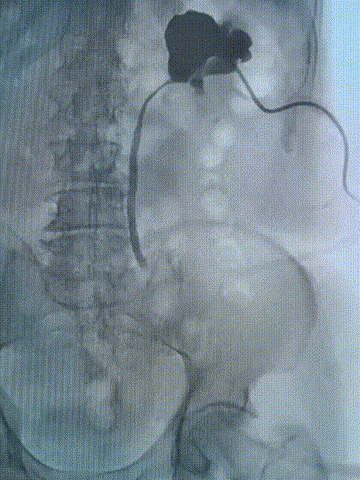

术后3月复查造影

术后3个月,患者按时返回医院复查,各项检查结果均显示良好:CTU检查提示输尿管通畅,无狭窄复发;血肌酐水平恢复正常,分肾功能良好;此前困扰患者的腰痛、血尿症状完全消失,目前已恢复正常工作和生活。